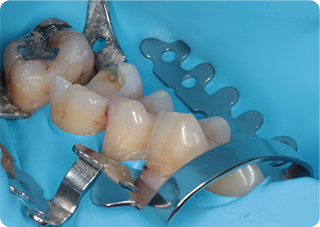

セラミックアンレー症例①

術前

むし歯除去

ラバーダム防湿

術後

| 主訴 | むし歯の治療をしたい |

|---|---|

| 治療期間/回数 | 2週間、2回 |

| 価格(税込) | 77,000円(税込) |

| リスク・副作用 | セラミックの破損、一時的な知覚過敏が生じる場合がある |

| ポイント | ラバーダム防湿をし、唾液や呼気の侵入を防ぎ湿度を下げることで、セラミックの接着力の向上を計った。接着力の向上により、脱離や破折の予防になる。 |